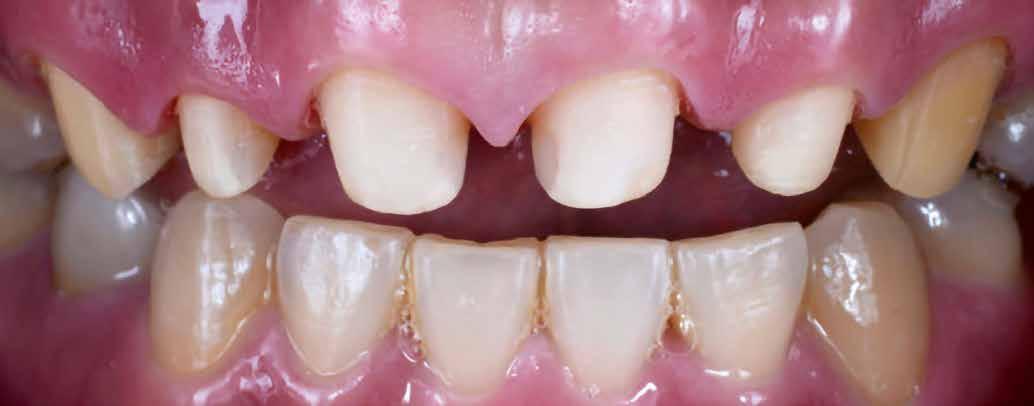

1. kép: Preoperatív szituáció.

Pácienseset

33 éves páciens konzultált a rendelőben 3 évig tartó fogszabályozása elemeinek eltávolításáról szájából. A kárieszek eltüntetésén kívül optimalizálni szerette volna esztétikai kinézetét. Az első esztétikai elemzés a frontfogak kedvezőtlen hossz-szélesség arányát mutatta (1. kép). A bal felső szemfogat a pulpa elhalása következtében endodonciai kezelésnek is alá kellett vetni.

Klinikai kezelés

A gyökérkezelést és a kárieszek megszűntetését követően kompozittömések készültek, majd preparálták a restaurálandó frontfogakat (3. kép). Ideiglenes koronák is szájba kerültek (4. kép), a jobb kismetszőt meghosszabbították. A fogínylefutás szimmetriáját az ideiglenes koronák megtámasztása segítette. A fogak és íny kívánt szimmetriáját elérve véglegesítették a preparációt (5. kép) és elkészültek a lenyomatok.